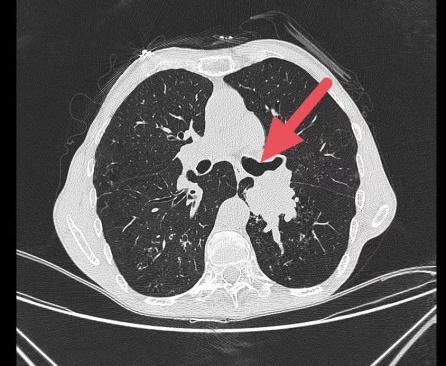

麻醉成功后,佘巍巍博士娴熟地为患者插入了硬镜,然后配合电子支气管镜下电圈套器切除、冷冻冻取、活检钳钳除及氩气刀等多种手段对肿瘤进行切除,历时30分钟左右,肿瘤完全切除,左侧的主支气管恢复通畅。术后,患者呼吸困难症状减轻,次日就可以自如的下床活动且没有明显气喘不适,复查肺部CT和气管镜示左侧气道通畅,左下肺已经复张,为患者后续治疗争取到宝贵的时间。

术后